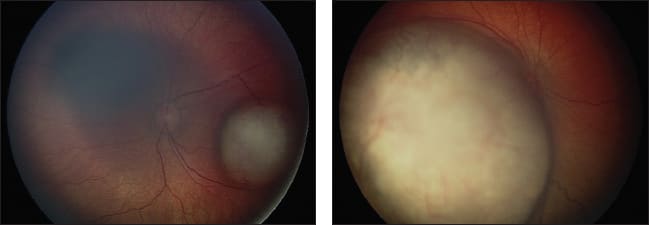

Figure 2. Left eye (left images) and right eye (right images) of a child with bilateral retinoblastoma before treatment (top images) and after bilateral intra-arterial melphalan and laser consolidation (bottom images).

For patients with bilateral disease, Abramson et al.9 also reported on the use of tandem therapy, or bilateral infusions, during the same session. In a report of four patients with advanced bilateral retinoblastoma (R-E stage V), all eyes avoided enucleation or radiation, without any serious adverse effects.